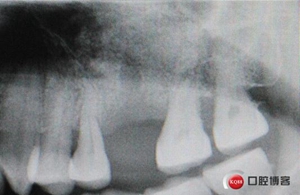

骨高度比曲斷片顯示的更低,不利于同期植入,直接縫合。

術(shù)后X光片,植骨量充足。

術(shù)后8個(gè)月,X光顯示骨量充足,密度明顯增加。